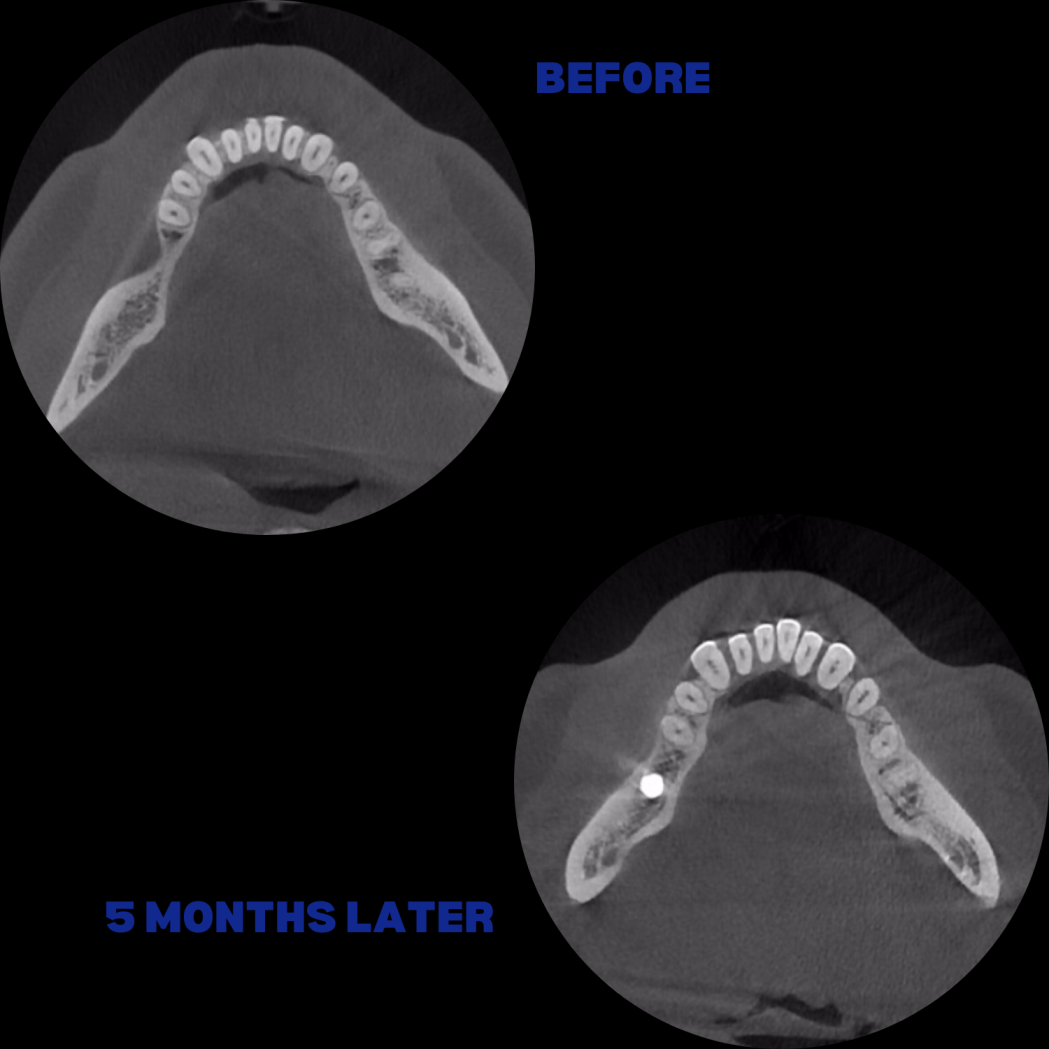

İmplant etrafındaki kemik açıklığını kemik grefti ile tedavi ettiğimiz vakamız